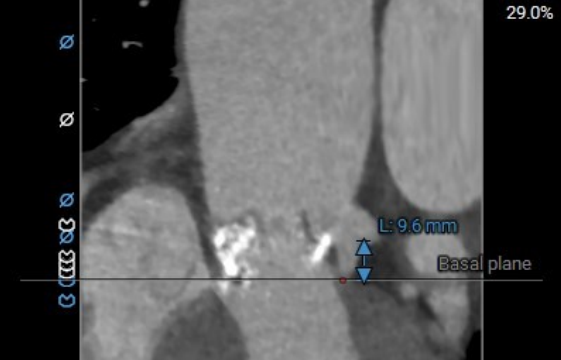

术前主动脉CTA评估:主动脉瓣三叶式,瓣叶基本等大,瓣叶增厚、黏连,瓣叶游离缘中-重度钙化,左-无、右-无交界钙化融合。主动脉瓣环周长折算直径约28.6mm;左侧冠脉开口高度稍低LCA:9.6mm,RCA:13.7mm;右冠及左冠分支轻度钙化;左室流出道轻度钙化。升主动脉增宽;双侧髂外动脉迂曲,余未见明显迂曲。

左冠高度:9.6mm